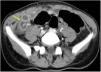

Niña de 11 años con síndrome de Down, que acude a urgencias por presentar dolor abdominal de predomino en fosa ilíaca derecha (FID) y fiebre de 48h de evolución. Entre los antecedentes encontramos enfermedad de Hirschsprung tratada mediante colostomía en el período neonatal y posterior descenso abdominoperineal tipo Duhamel, presentando varios episodios de oclusión intestinal posteriores que se resolvieron con tratamiento conservador. A su llegada presentaba regular estado general, fiebre de 39°C, el abdomen era blando y depresible, con dolor intenso y defensa muscular a la palpación de la FID. La analítica sanguínea demostró leucocitosis con neutrofilia y una PCR de 15,5mg/dl. Se realizó ecografía abdominal objetivándose una estructura tubular fija en la FID con paredes engrosadas y contenido líquido (figs. 1 y 2). El estudio se completó con una TAC abdominal confirmándose el diagnóstico de hidropiosalpinx derecho (fig. 3). Se inició antibioterapia endovenosa con amoxicilina-clavulánico objetivándose mejoría clínico-radiológica en las primeras 24h sin precisar drenaje quirúrgico de la colección. Se dio de alta a las 72h con antibioterapia oral y buena evolución posterior.